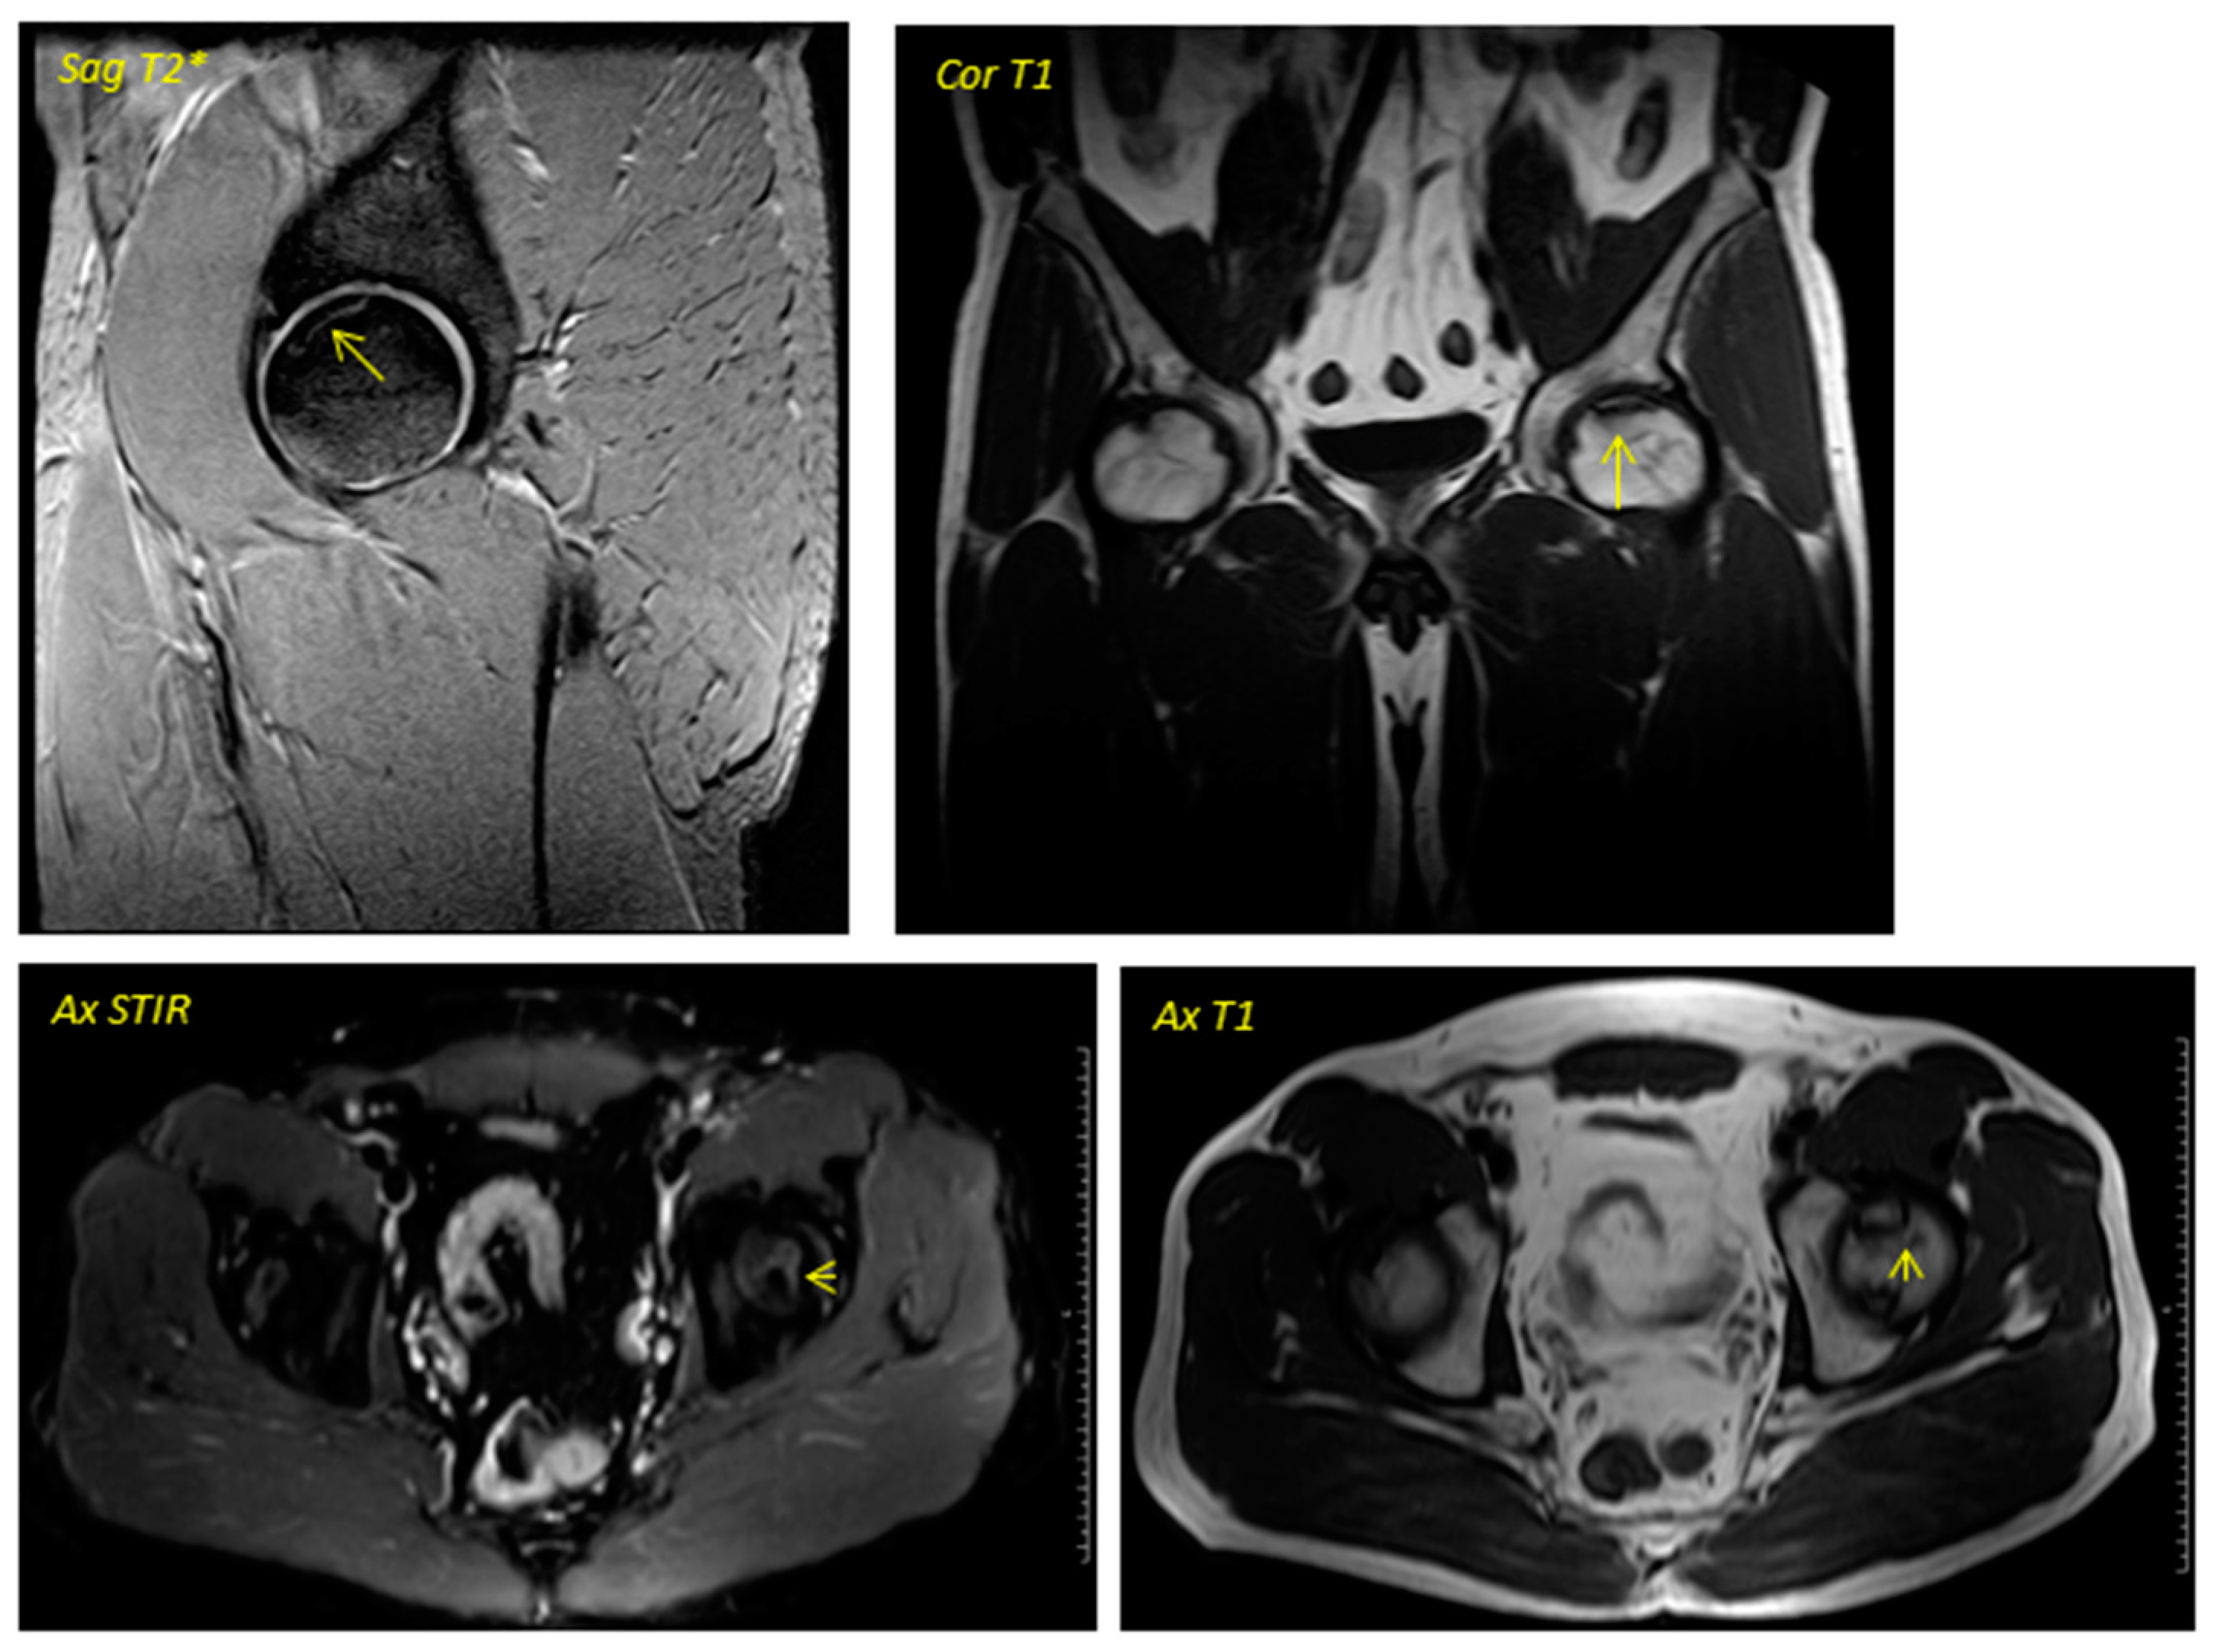

關于影像學研究,在12個月的隨訪期間,在影像學演變中觀察到了一些發現(圖1和圖2)。

首先,方向的變化從第六個月開始出現在所有病例中,而在早期階段并不明顯。其次,62.5%的患者 ( n=5) 在手術后的第一年內實現了影像穩定。第三,兩名患者 (25%) 出現壞死區進展,而一名 (12.5%) 患者出現明顯的再骨化跡象。盡管觀察到描述性差異,但后一個參數的p值在統計學上并不顯著。